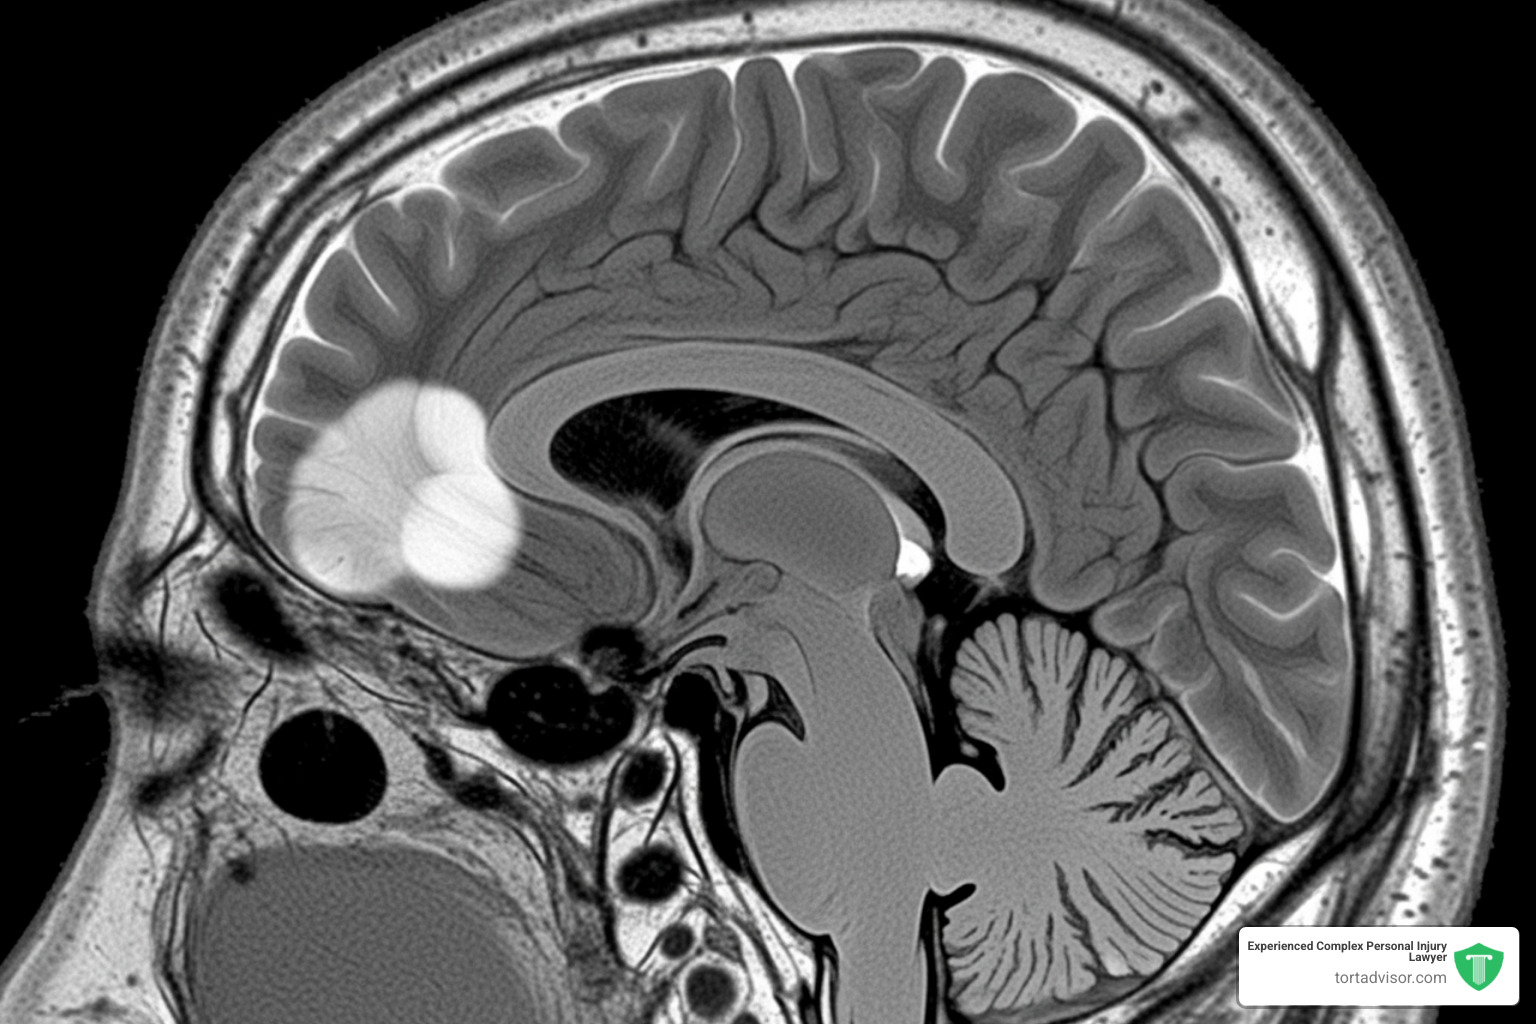

What is a Meningioma Brain Tumor?

A meningioma is a tumor that grows in the meninges—the protective membranes wrapping your brain and spinal cord. When a tumor forms there, it’s called a meningioma.

These tumors are the most common type of primary brain tumor, accounting for about 40% of all diagnoses. Most meningiomas are benign (non-cancerous) and grow slowly. However, even a benign tumor can cause serious problems if its size creates pressure against the brain, spinal cord, or nerves.

That pressure can trigger a range of neurological symptoms. What makes this particularly relevant to Depo-Provera users is that meningiomas occur more frequently in women than men, pointing to hormonal influences.

If you’re experiencing any of these symptoms, especially if they’re new or worsening, seek medical attention immediately. Meningiomas are typically diagnosed through an MRI. While many are treatable with surgery, some are inoperable and require radiation or other treatments, which can reduce quality of life. Early diagnosis offers the best chance for effective treatment and provides the strongest foundation for a depo provera injury claim.